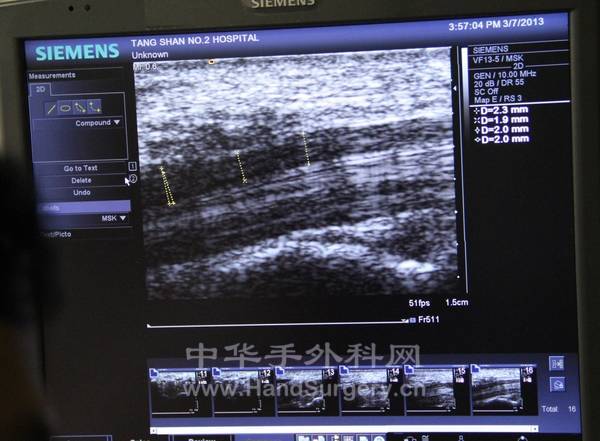

彩超室

主任给我讲解图像显示内容

彩超辅助诊断腕管综合征

正中神经受到腕横韧带卡压

中间变细,D=1.2

两侧变粗,D=1.9,2.1

标记的是正中神经

上边浅层是腕横韧带

下边白色的是屈肌腱